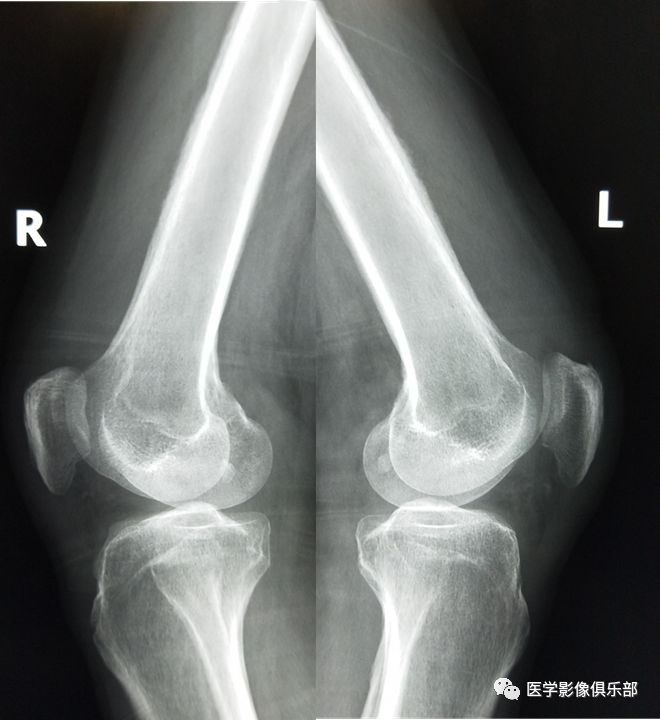

股骨下段病变大家看看是什么

股骨病变哦原来是它